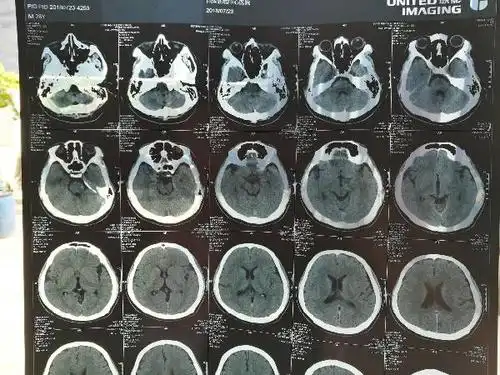

宝宝出生第二天开始抽搐然后拍ct发现颅内出血,请帮忙

请问哪位一生可以帮我看看这张脑ct片子有什么问题?

今天早上狠狠的摔了一跤,是头部着地的,过后头接触地

我是医师,但对脑科可是菜鸟,请高手解惑.